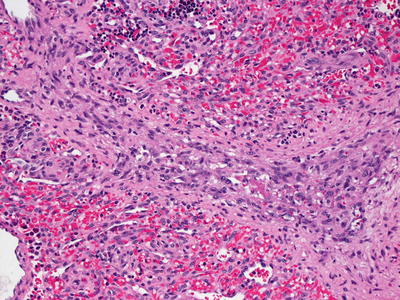

The cutaneous histologic changes of KTS are indistinguishable from those seen in port-wine stains not associated with limb hypertrophy. Ectatic thin-walled capillary vessels are present initially in the superficial dermis. With time, the vascular lesions become progressively dilated, and the vessel walls have greater thickness. Vessels deeper in the dermis are also affected. Thrombi may be present in congested vessels. These lesions can become nodular and are likely to recur [122]. In rare cases, angiokeratomas have been described in patients with KTS [123].

Secondary changes, such as spongiotic dermatitis with inflammation (Meyerson’s phenomenon ) and acro-angiodermatitis (marked stasis changes or pseudo-Kaposi’s sarcoma) are found in some patients with KTS. The spongiotic changes include intraepidermal edema and lymphohistiocytic infiltrate [16]. Acro-angiodermatitis is characterized by proliferation of slit-like vascular spaces and lobular proliferations of markedly thick-walled vessels. There is abundant extravasation of erythrocytes and hemosiderin deposition. The histologic changes are those of prominent stasis dermatitis [124]. A subset of patients with KTS vascular lesions have associated pigmented lesions, and thus have the designation of phakomatosis pigmentovascularis type IIb [2, 125].